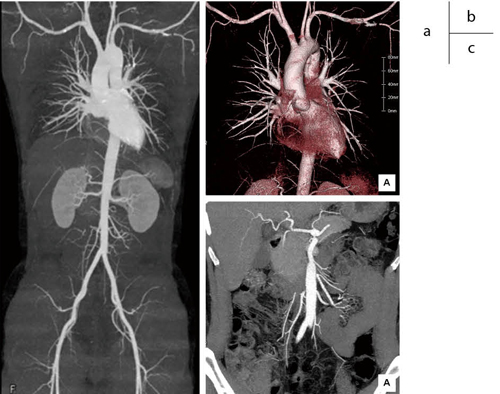

0.35秒/回転を用いた、胸部から骨盤までの大血管撮影(撮影時間:5秒)

a:MIP画像 b:VR画像 c:Slab MIP画像

高速回転による短時間撮影であるが、細部の血管まで描出されていることがわかる。